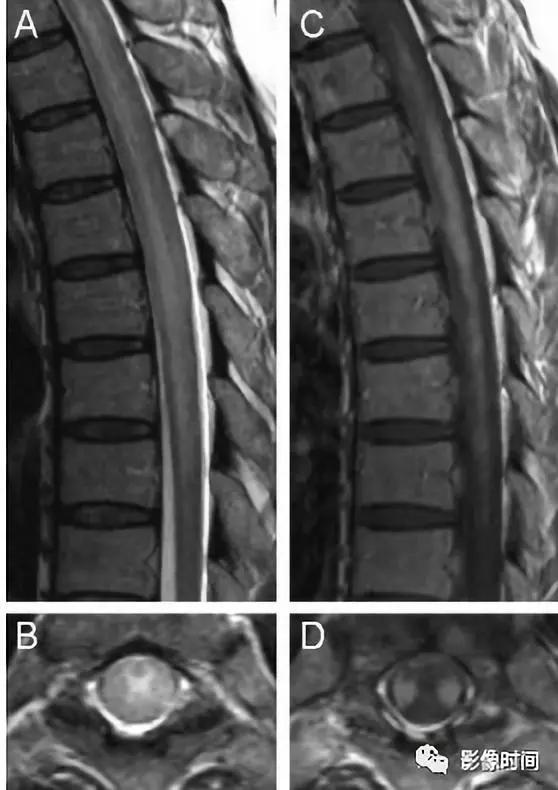

硬脊膜动静脉瘘 (spinal dural arteriovenous fistula,SDAVF):供应脊膜或神经根的细小动脉,在椎间孔处穿过硬膜与脊髓引流静脉相通,导致脊髓回流受阻。病因不明,成人-老年人胸腰段多见,缓慢起病,进行性加重。

MRI:

-

矢状位 T2WI 发现长节段高信号

矢状位 T2WI 脊髓周围流空低信号血管影

部分可见强化,提示血脑屏障破坏

脊髓内长节段T2WI高信号,髓周可见多发点状流空血管,增强扫描出现强化